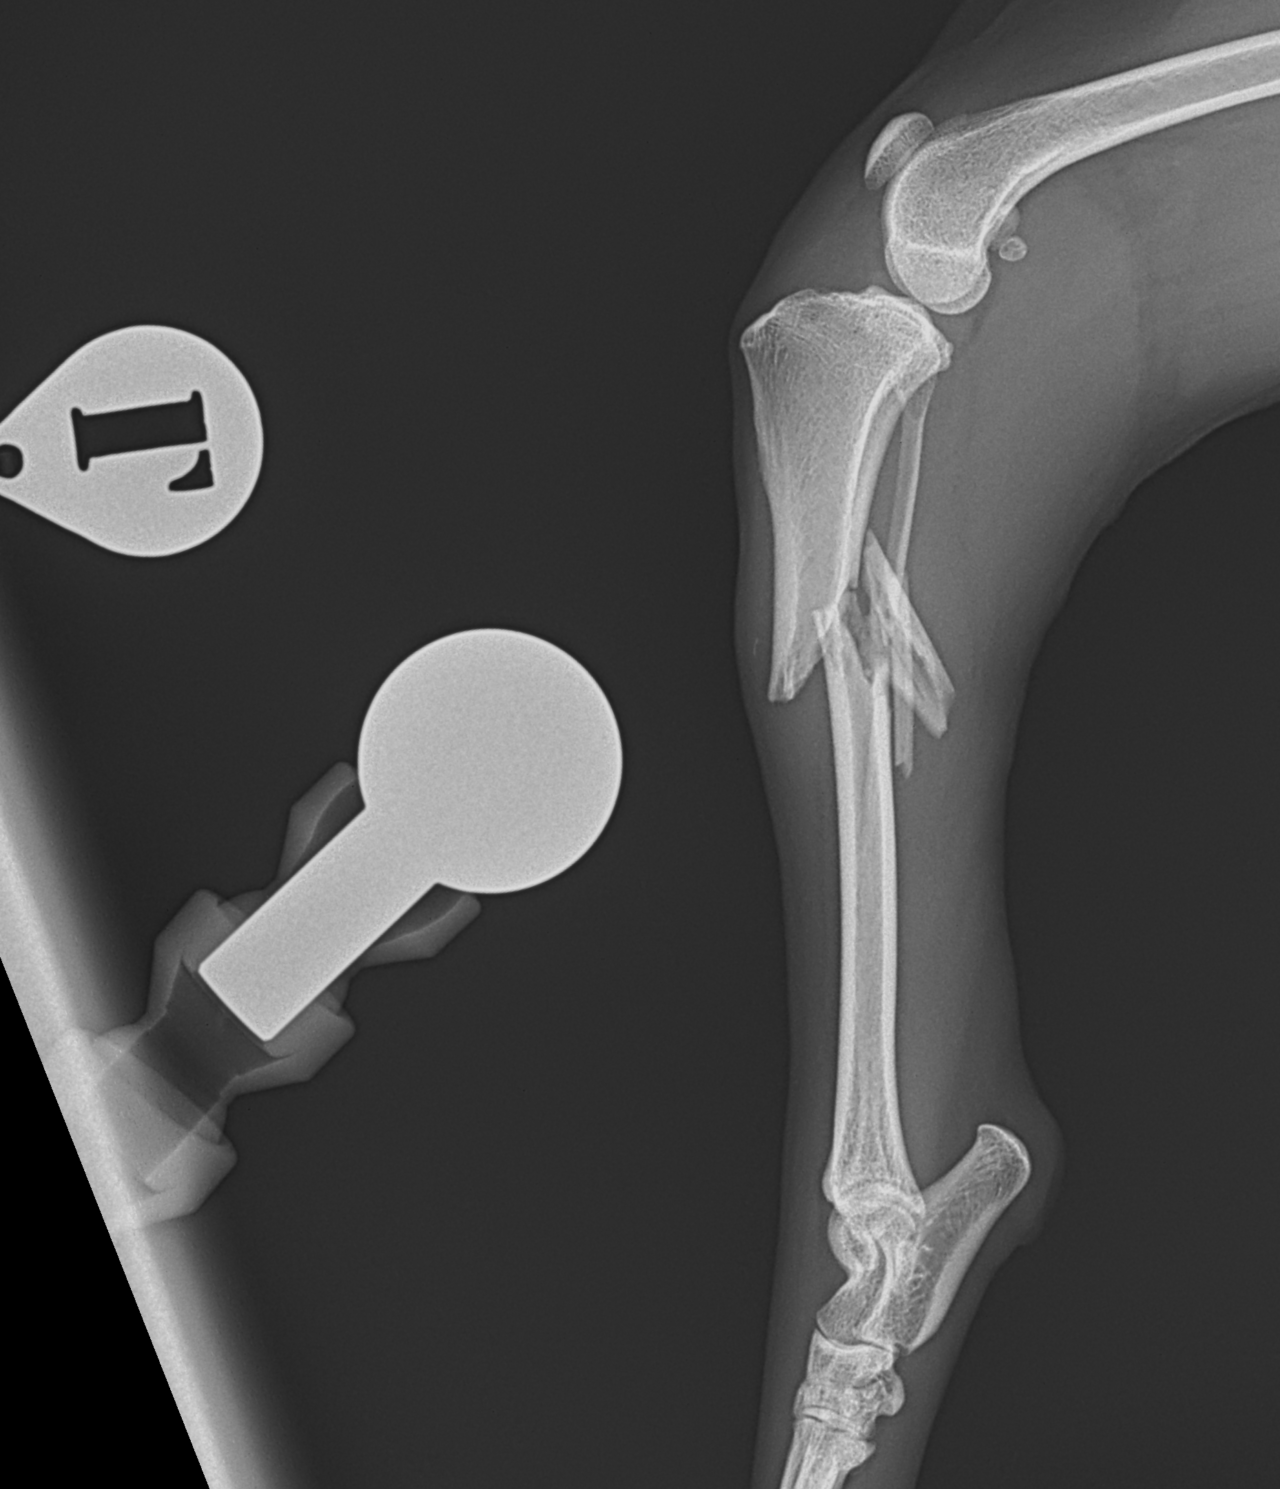

脛骨粉砕骨折

13歳のトイ・プードルがソファーからジャンプした際に後肢を傷めて救急病院を受診されました。エックス線検査で脛骨近位部の粉砕骨折(comminuted tibial fracture)が確定され、骨固定術の依頼がありました。小型犬では、ソファーやベッドなどの高さからのジャンプでも骨折が起こることがあります。特に高齢になると、骨密度の低下、骨皮質の菲薄化などにより、比較的弱い外力でも骨折が起きやすくなるため注意が必要です。今回の患者さんではOrthogonal ロッキングプレート固定+髄内釘(Plate–Rod construct)により骨折部を安定化しました。粉砕骨折では骨片を無理に整復せず、生物学的固定(biologic fixation)により自然な骨癒合を促す方法が現在の主流です。高齢犬でも適切な固定を行えば、良好な骨癒合と歩行回復が期待できます。